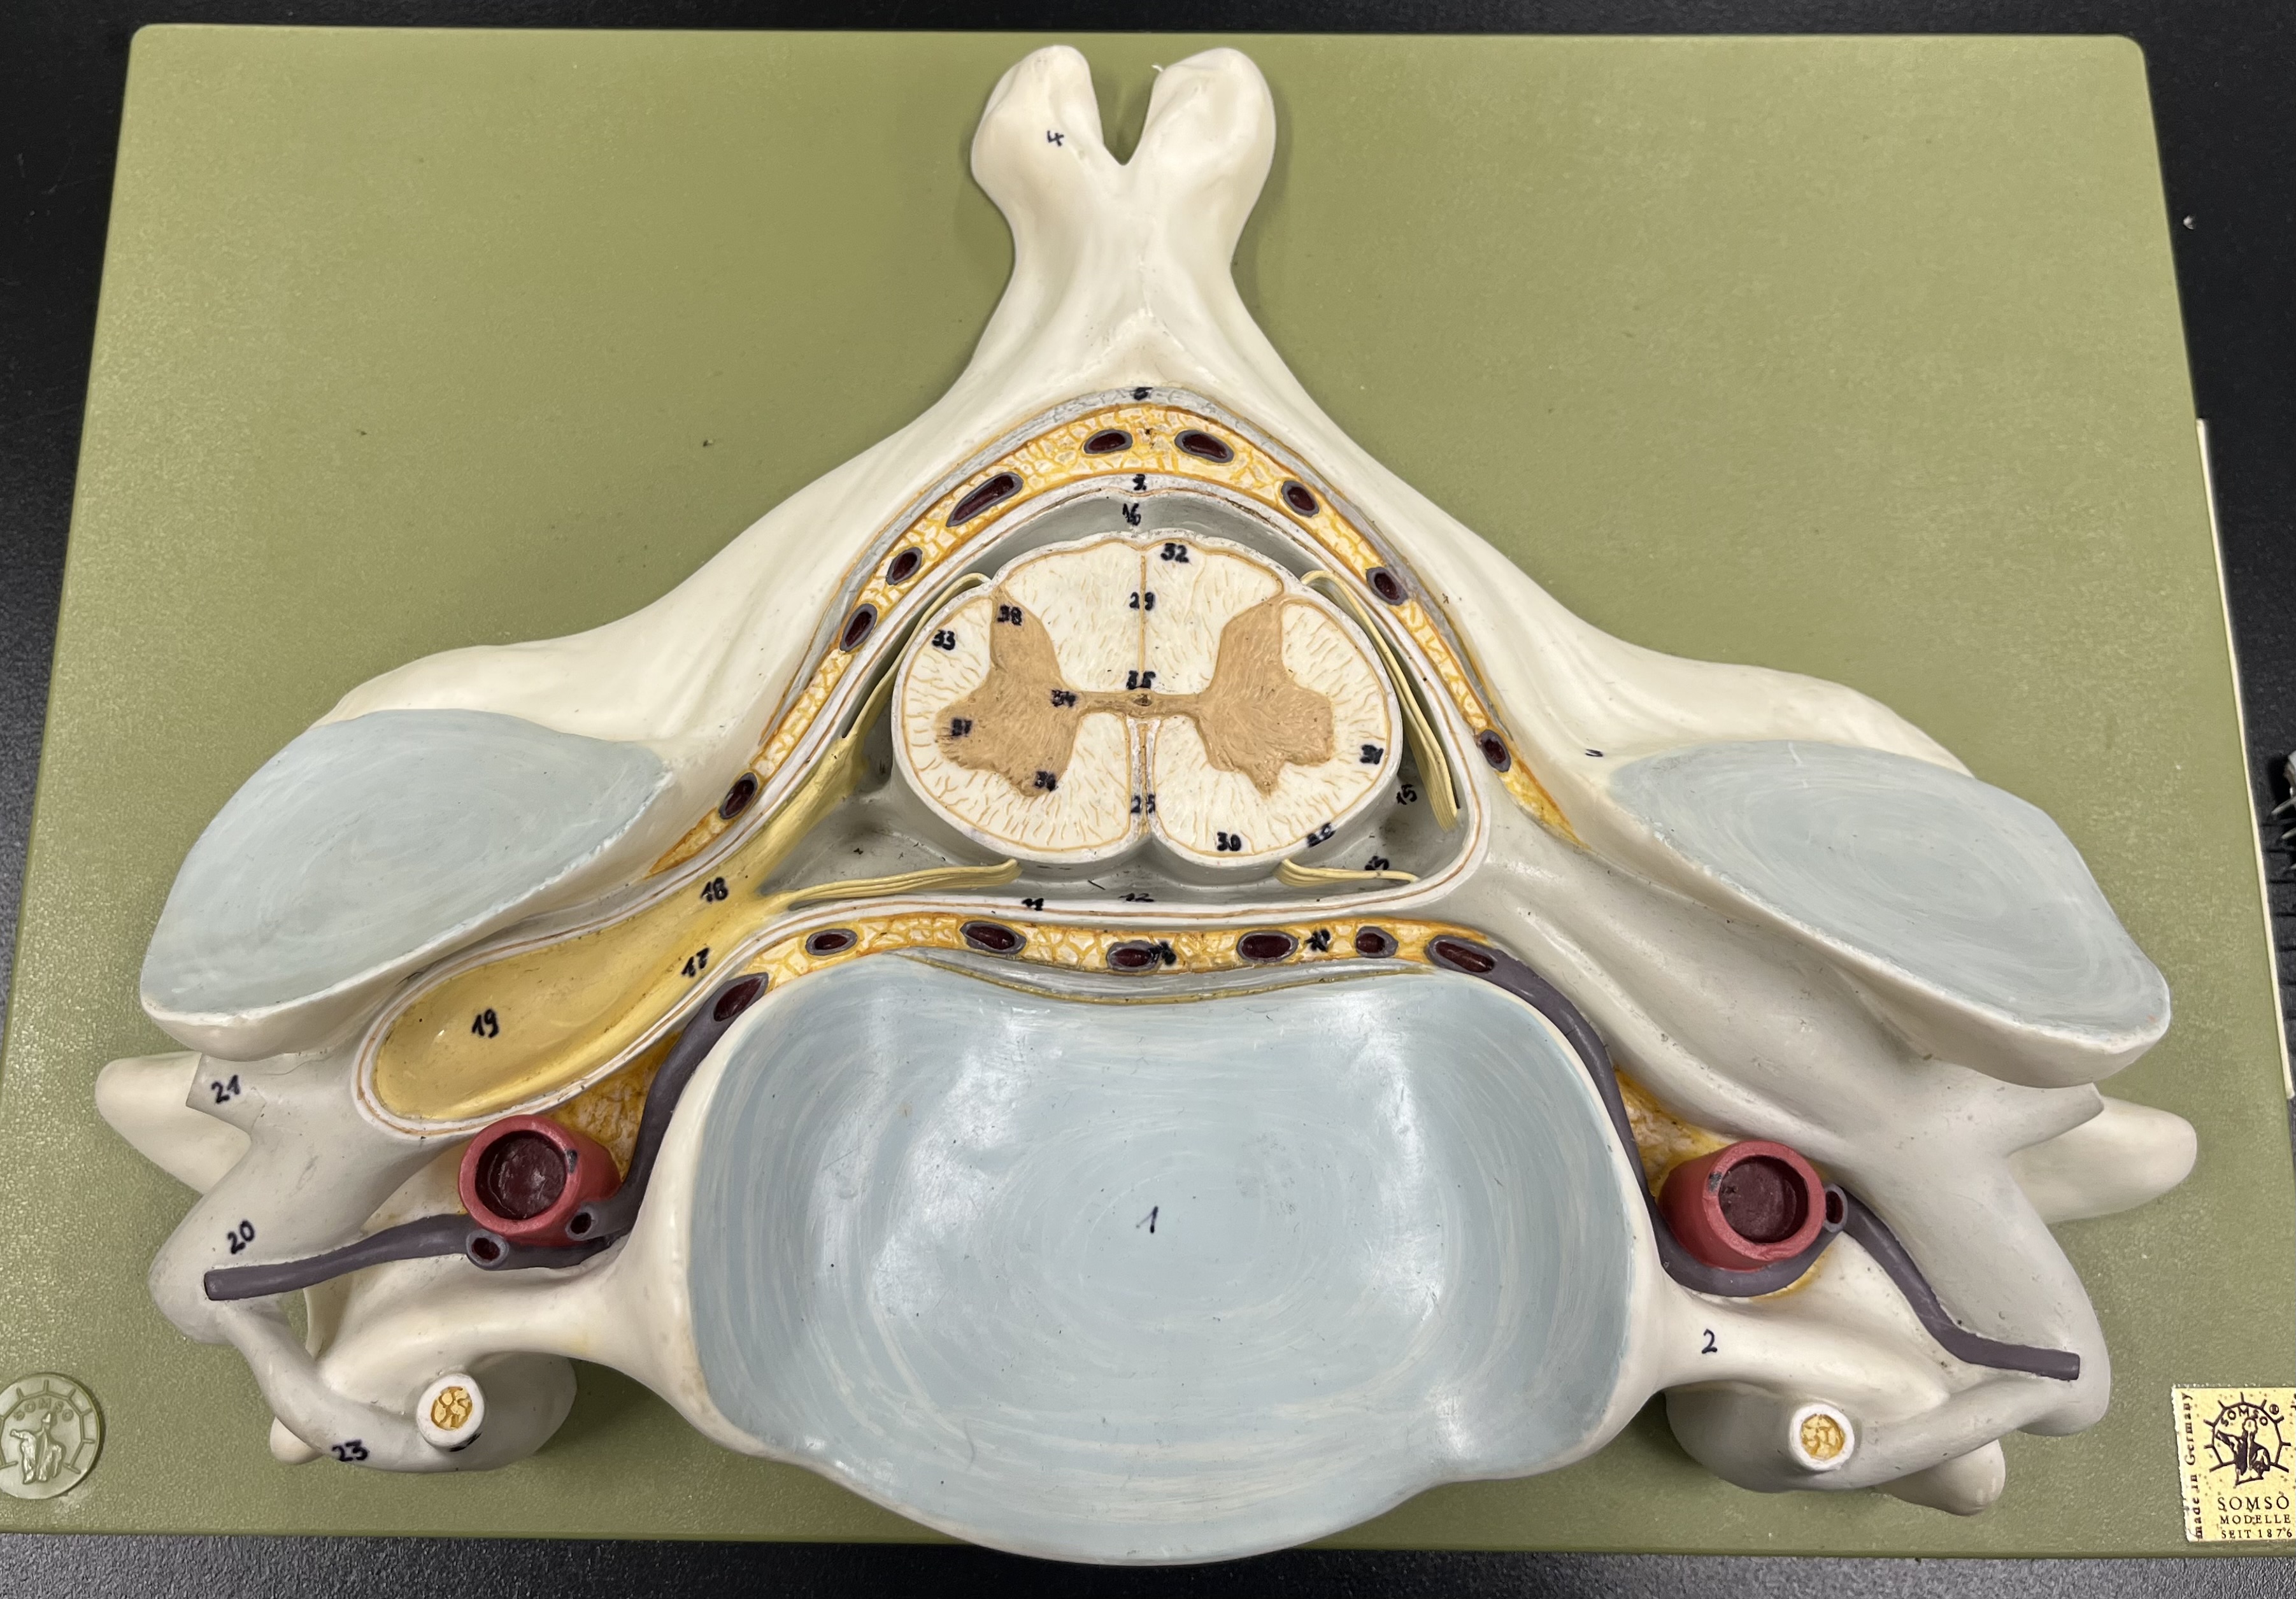

epidural space

dura mater

subdural space

arachnoid mater

subarachnoid space

pia mater

denticulate ligaments

What is the groove here?

anterior median fissure

posterior median sulcus

posterior (dorsal) horn

anterior (ventral) horn

lateral horn (selected models)

gray commissure

central canal

anterior column

lateral column

posterior column

white commissure

posterior (dorsal) root ganglion

What is the bulb here?

posterior (dorsal) root ganglion

posterior (dorsal) root

posterior (dorsal) root

anterior (ventral) root

anterior (ventral) root

dorsal ramus

dorsal ramus

ventral ramus

ventral ramus

rami communicantes

rami communicantes

sympathetic chain ganglia

sympathetic chain ganglia